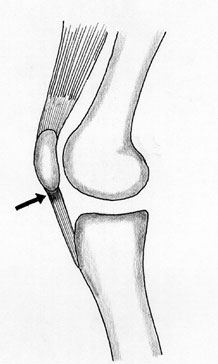

Lesões Meniscais do Joelho

Os meniscos são estruturas fibrocartilaginosas no joelho com diversas funções:

- Amortecimento

- Transmissão de forças

- Absorção de choque

- Estabilidade articular

- Lubrificação articular e nutrição

- Propriocepção

Pacientes com lesões meniscais frequentemente sentem dor na linha articular, associada a bloqueio articular e sensação de instabilidade (falseio).

Tratamento

A vascularização do tecido meniscal é crucial para o planejamento do tratamento. Apenas o terço periférico do menisco é vascularizado, o que significa que lesões fora dessa área têm baixo potencial de cicatrização. A preservação do tecido meniscal é fundamental para manter o equilíbrio articular. Mesmo em lesões com baixo potencial de cicatrização que exigem meniscectomia (remoção meniscal), busca-se remover a menor quantidade possível de tecido.

- Pacientes submetidos à sutura meniscal devem evitar flexões maiores que 90 graus por 45 dias e são liberados para atividades esportivas após 6 meses da cirurgia.

- Pacientes submetidos à meniscectomia parcial são liberados para apoiar precoce e geralmente retornam às atividades físicas após 60 dias. É importante ressaltar que o tempo de recuperação pós-operatória varia e deve ser analisado caso a caso com o médico especialista.